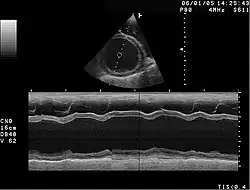

W celu zdiagnozowania choroby wykonuje się przede wszystkim następujące badania: echokardiografię, elektrokardiografię (EKG), biopsję endomiokardialną oraz cewnikowanie serca.